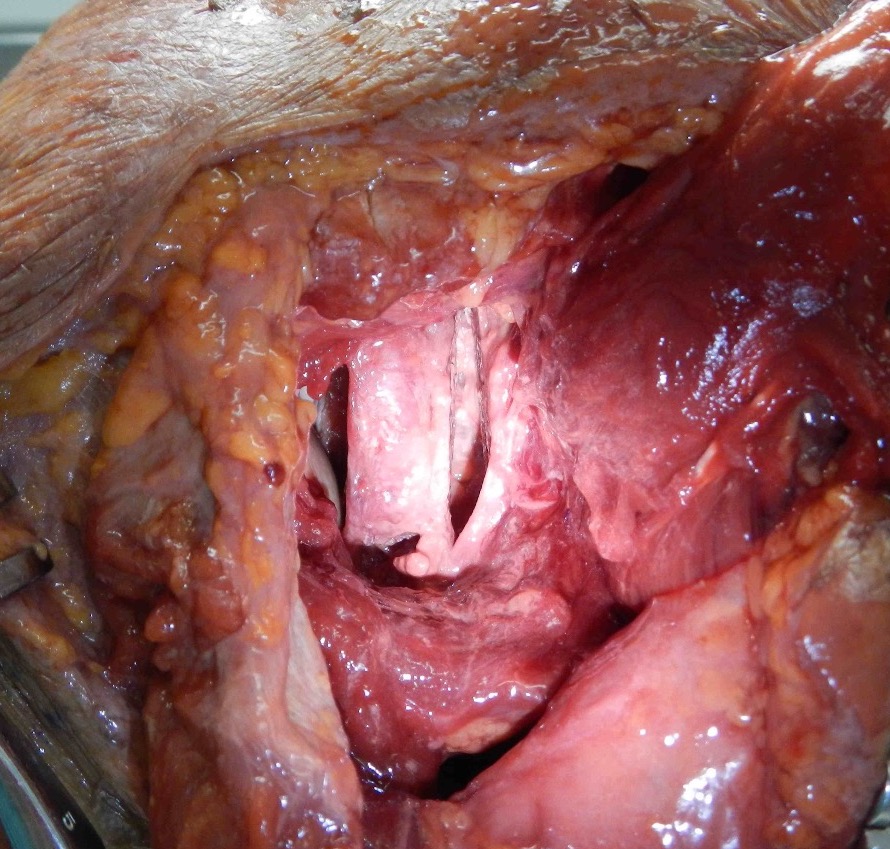

Identify and elevate deltoid / detach from scapular spine / identify infraspinatus

Identify interval between infraspinatus and teres minor, detach and reflect infraspinatus to expose posterior capsule and glenoid